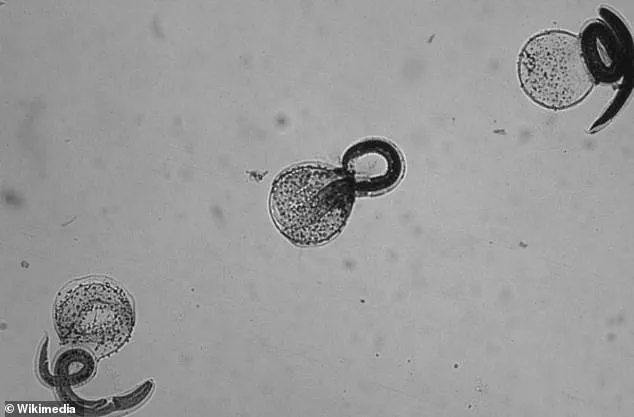

The B. procyonis infection is caused by the roundworm Baylisascaris procyonis, which is primarily found in raccoons but can also be transmitted through the feces of infected domestic dogs.

The parasite’s life cycle involves raccoons ingesting eggs, which then develop into larvae and are shed in their feces.

When humans or animals come into contact with contaminated feces—often through hand-to-mouth contact or ingestion of soil or water containing the eggs—the larvae can migrate to various organs, including the brain, where they cause severe neurological damage.

Raccoons, as noted by health officials, become infected by ingesting eggs during foraging or by consuming infected animals like rodents and birds.

Once inside the raccoon’s body, the parasite matures, producing eggs that are excreted in feces.

These eggs can persist in soil for years, creating a hazard for humans who come into contact with contaminated ground.

The parasite’s larvae, once ingested, can travel through the bloodstream and invade organs, including the brain and eyes, leading to severe complications.